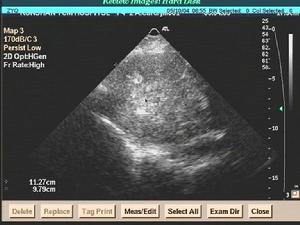

2.彩聲都卜勒超心動圖檢查可顯示突出於心包的腫塊和心包積液。